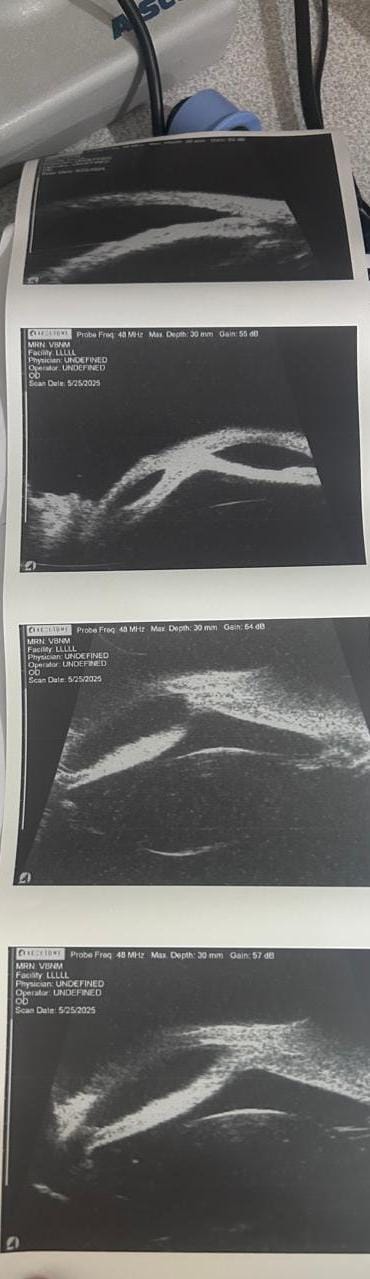

أعلن الدكتور حمودة الجزار، وكيل وزارة الصحة بالدقهلية، عن تشغيل جهاز UBM – Ultrasound Biomicroscopy داخل مستشفى رمد المنصورة، مؤكدًا أن تشغيل الجهاز يُعد نقلة نوعية في مجال التشخيص الدقيق لأمراض العيون، بما يسهم في الارتقاء بجودة الخدمات الطبية المقدمة للمرضى.

وأوضح وكيل الوزارة أن الجهاز يُمكّن الأطباء من فحص وتشخيص أدق تفاصيل العين، والتعرف على أورام العين الأمامية، وتقييم حالات المياه الزرقاء (الجلوكوما)، وتشخيص الأمراض الناتجة عن النمو غير المكتمل للمنطقة الأمامية للعين، بالإضافة إلى إجراء الفحوصات اللازمة قبل زراعة القرنية.

من جانبه، أكد الدكتور أحمد حسان، مدير مستشفى الرمد بالمنصورة، أن الجهاز بدأ بالفعل في استقبال الحالات داخل وحدة الفحوصات بالمستشفى، تحت إشراف نخبة من الأطباء المتخصصين في طب العيون، من بينهم الدكتور أحمد سليم، والدكتور إسلام عبد الهادي، والدكتورة رنوي مختار، والدكتورة أماني محمد علي، والدكتورة ريم غازي، مشيرًا إلى أن المستشفى يستقبل جميع الحالات المحولة من مختلف المراكز والمستشفيات بالمحافظة.